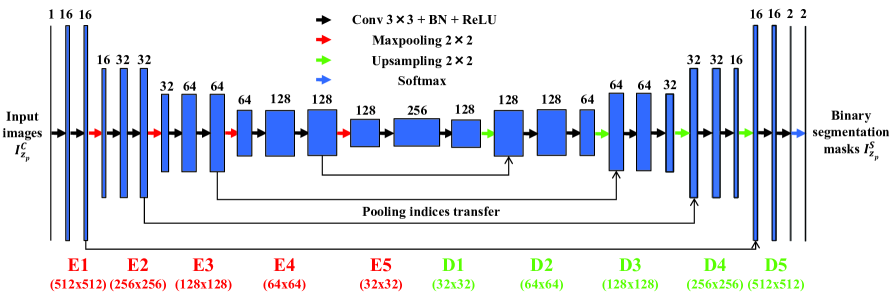

The architecture of our convolutional neural network, shown in Figure 2, consists of encoder layers denoted as through and decoder layers denoted as through that are serially connected followed by a softmax layer at the end. Each encoder layer consists of a kernel with pixel padding to maintain same image size, a batch normalization step [29] to perform image whitening, followed by a rectifier-linear unit (ReLU). The combination of convolution, batch normalization, and ReLU are performed twice at every encoder. Finally, maxpooling with a stride of is used to reduce dimensionality. This encoder scheme is similar to VGGNet [30] which shrinks the input dimensions but increases the number of filters in the deeper structures. In Figure 2, each encoder’s input dimension is indicated in red under the encoder layers. Also note that the number shown above each layer represents the number of filters utilized for training. For example, an input image of size is resized to at the input to the E2 layer. As the image passes through the all encoder layers, its X and Y dimensions shrink to , respectively, but number of filters utilized increases to . Therefore, the input to the first decoder layer is of dimension .

Conversely, each decoder is comprised of two kernels with pixel padding, batch normalization, and ReLU. Instead of a maxpooling layer, the decoder has an unmaxpooling layer to upsample the data to increase dimensionality. Note that this upsampling process is a reconstruction process. To achieve better upsampling maxpooling indices from each encoder layer are recorded and transferred to the corresponding same size unmaxpooling layer (). At the end of the encoder-decoder structure, a softmax classifier layer is utilized to determine whether each pixel location belongs to a tubule or background using a probability map. Note that the output of the softmax layer is of size because the final output includes two probability maps corresponding to the two classes: tubule or background. These probability maps are thresholded at to produce binary segmentation masks.

During the training stage augmented training images () are randomly selected and used to train the model for each iteration. The segmentation mask is compared with the corresponding groundtruth () and a loss value is obtained for each iteration. Here, we use a 2D cross entropy loss function that is minimized using stochastic gradient descent (SGD) with a fixed learning rate and a momentum. During the inference stage we use the trained model with test images () to obtain binary segmentation masks (). During the postprocessing step we clean up objects less than pixels from followed by a hole filling operation to obtain final segmentation results (). Note that the hole filling operation assigns a background pixel to a tubule pixel if the background pixel’s neighborhood pixels are all tubule pixels.